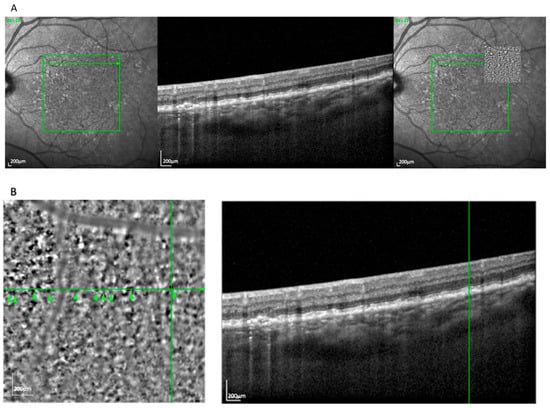

The spot pattern appeared in 39 eyes (32.5%) and consisted of a homogeneous distribution of small, bright clusters (typically 20–50 per image) without a defined border (Figure 2). These were associated with pre-atrophic changes in the OCT, such as localized RPE disruption and early photoreceptor irregularities. Notably, this pattern was observed in both the nvAMD and dry AMD subgroups, consistent with its representation of an early degenerative phenotype. The spot pattern showed features consistent with iRORA, including RPE irregularity and early photoreceptor disruption. This pattern occurred more often in GA (69.2%) than in nvAMD (30.8%).

Figure 2.

(A) Correlation of spot lesions visible on an AO-TFI image in RPE mode with the OCT finding using vessel structure for orientation. (B) Visualization of spots and high-magnification view of the correlated pre-atrophy zone. The green arrowheads indicate prominent hyperreflective clusters forming the “spots” pattern.